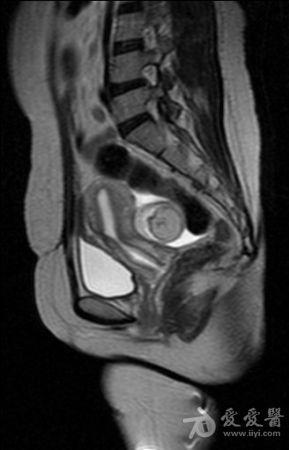

体检发现盆腔包块入院检查(较典型病例MRI平扫加增强)。

病史如题。图像如下。 T2

含有脂质信号,边缘清楚,考虑畸胎瘤